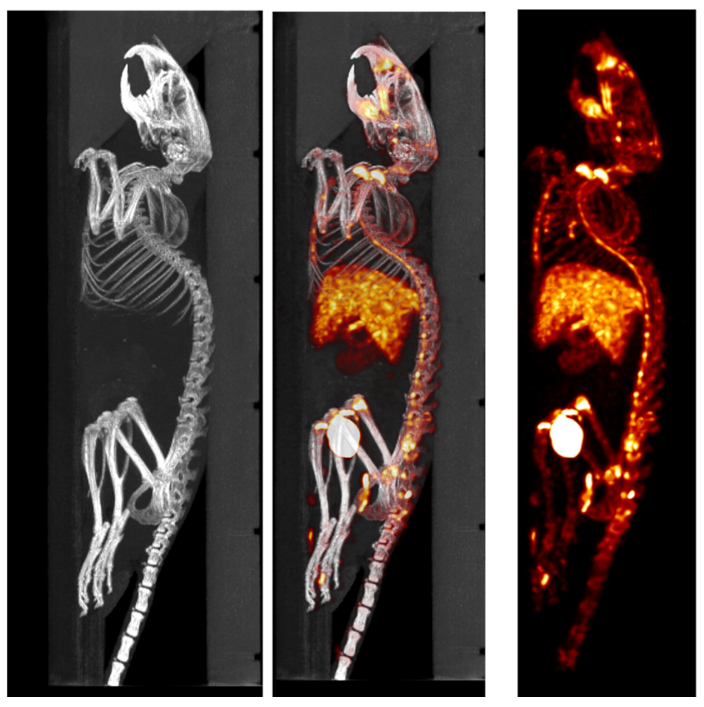

3、骨骼SPECT成像

SPECT/CT組合圖像,小鼠的骨骼成像:99mTc-HDP,94.35MBq (2.55mCi) @ start acquisition,采集時(shí)間60min。

骨骼成像.png

SPECT/CT組合圖像,大鼠的骨骼成像:99mTc-HDP,200MBq,采集時(shí)間45min。